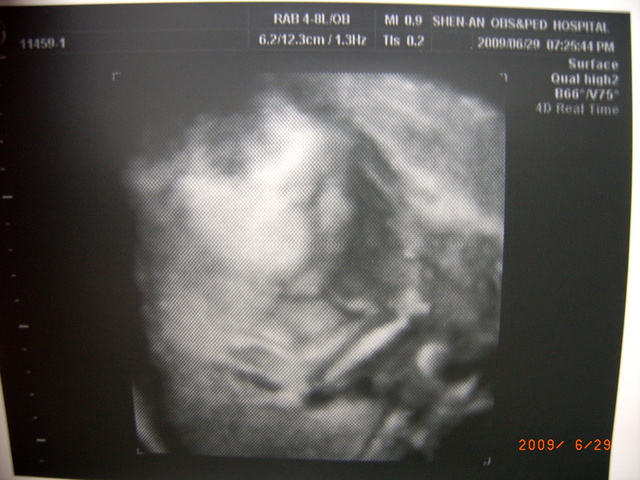

接下…看看4D吧…

真的超像流氓小候的啦…(怎像到他哩= ="")

是院列印的黑白4D啦…

是我DVD抓的彩色4D…

看照片的人都…怎肉啊…哈哈…

Baby的小丫…很清楚…有五指…

29W1D…Baby有1,519G...